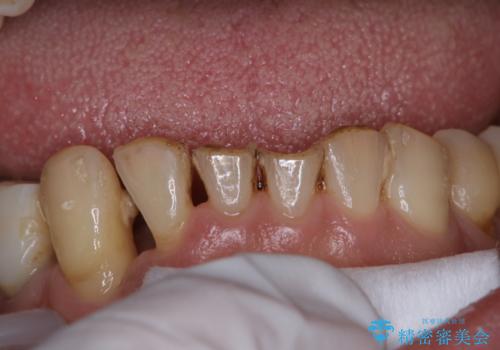

- 治療中のメンテナンス希望の方です。PMTC30分コースを行いました。

口の中には、目には見えない細菌がたくさんいます。歯周病は細菌による感染症です。歯面のプラークや着色(ステイン)など、細菌をしっかり除去し、治療の妨げにならないよう、治療中にPMTCを行うことも大切です。